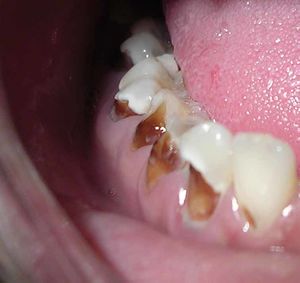

حدوث التسوس وتطوره

تقوم الحموض الناتجة من عملية تخمر السكاكر بحل العناصر المعدنية والعضوية التي تدخل في تركيب ميناء السن فتبدو المنطقة بيضاء طبشورية وذات ملمس خشن. ولدى تزايد إنتاج الحموض وعدم تطبيق الفلوريد الموضعي على الأسنان الذي يقوم عادة بإيقاف تطور التسوس، يتهدم الميناء وتصل الإصابة إلى العاج مشكلة حفرة التسوس التي يمكن ملاحظتها سريرياً ويبدأ الإحساس بالألم لدى التعرض إلى مؤثرات خارجية من سخونة وبرودة أو الضغط أثناء المضغ. عند إهمال معالجة التسوس في هذه المرحلة يزداد التخرب وتصل الإصابة إلى لب السن الذي يصاب بالالتهاب وترافقه موجات حادة من الألم وخاصة في أثناء الليل. إن عدم تطبيق المعالجة الملائمة في هذه المرحلة يؤدي إلى تموت اللب وإصابته بالتعفن وتتكون الخراجات الحادة والمزمنة والآفات الذروية التي تنتهي بقلع السن المصابة.

هو تخرب يصيب نسج السن الصلبة بدءاً من طبقة الميناء enamel ثم يصل إلى طبقة العاج محدثاً حفرة قد تزداد اتساعاً وعمقاً لتصل إلى اللب الذي يحتوي الأوعية الدموية والأعصاب.